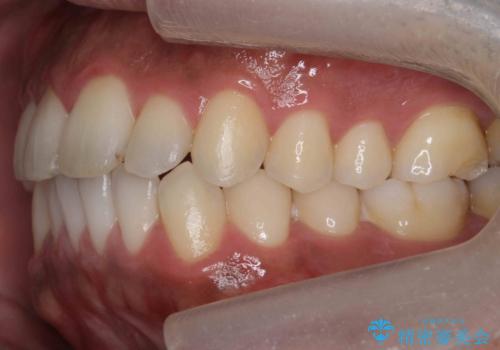

前歯が反対にかんでいる 部分ワイヤーとインビザラインの併用で短期治療

- 前歯の並びを気にして来院。

前歯が一本奥に入っているのを乗り越えるにはワイヤー矯正が治療期間も短く、歯に負担が少なく有利と説明しました。

上はワイヤー部分矯正、下はインビザラインの部分矯正コースを行いました。